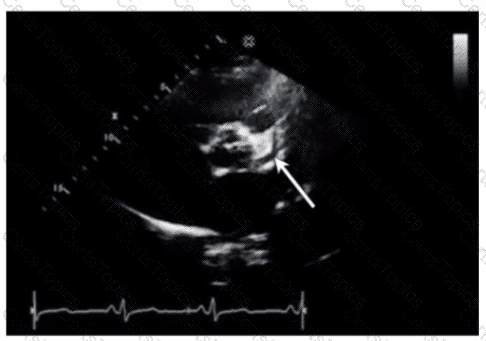

Which condition is most plausible based on the finding indicated by the arrow on this image?